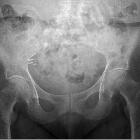

Clips im

rechten Unterbauch bei Zustand nach Appendektomie. Röntgenbild.